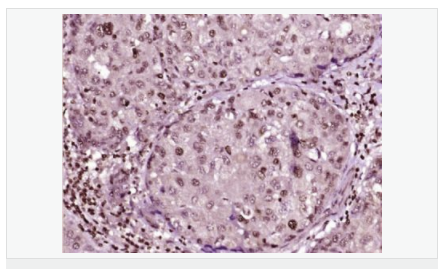

交叉反應:Human,Mouse,Rat(predicted:Dog,Pig,Rabbit,GuineaPig) 推薦應用:IHC-P,IHC-F,ICC,IF,Flow-Cyt,ELISA

| 產(chǎn)品應用 | ELISA=1:5000-10000 IHC-P=1:100-500 IHC-F=1:100-500 Flow-Cyt=1μg/Test ICC=1:100 IF=1:100-500 (石蠟切片需做抗原修復) not yet tested in other applications. optimal dilutions/concentrations should be determined by the end user. |